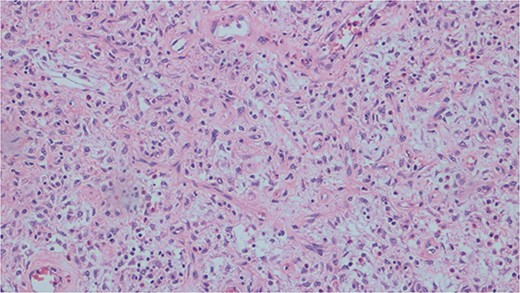

Histopathological analysis of the excised bowel segment revealed a low-grade, mural based spindle cell neoplasm (Fig. 5) with surrounding benign, reactive lymphadenopathy. The sample was sent for further immunohistochemical analysis for definite subtyping which demonstrated that the lesional cells stained positive for Vimentin, SMA and CD34. Desmin, S100, cytokeratin DOG-1, C-KIT, and ALK-1 were negative (Fig. 6). These findings were consistent with IFP in terms of morphology and immunohistochemical profile.

Histopathological slide demonstrating bland mesenchymal cells with a rich eosinophilic infiltrate.

Intussusception is a rare in adults, accounting for only 1% of bowel obstructions [1]. Of this small cohort however, a pathological lesion is found to act as a lead point in >90% of cases [2]. Such pathological lesions range from benign strictures to malignant tumours with the latter comprising of a concerningly high proportion of intussusception in adults—40% and 17% in the large and small bowel respectively. Differentiating between benign and malignant causes of intussusception can be challenging both pre-operatively and intra-operatively as well as from a histopathological perspective as seen in this case. IFP has been previously termed ‘the great mimicker’ due to its close resemblance to invasive masses such as spindle cell tumours [8] which carry a 40%–50% mortality rate when found in the small bowel [9]. Immunohistochemistry provides a useful means of definite subtyping with most IFP lesions staining positive for CD34 and, to a lesser extend vimentin and CD117 [7, 10, 11]. However, no immunohistochemical stain has proven effective in definitively identifying IFP to date.